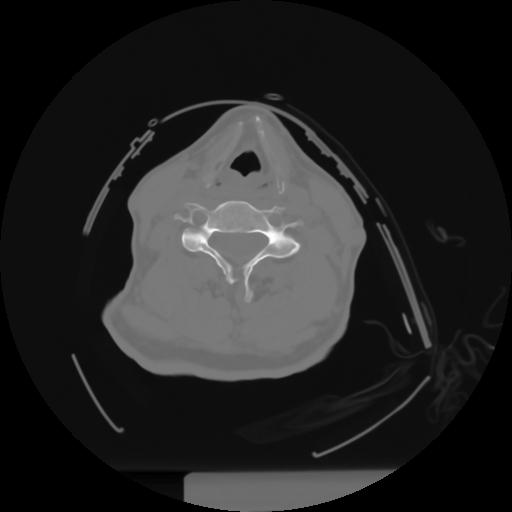

10 P.BLANDAS,,Axial,2.0,P.BLANDAS,,